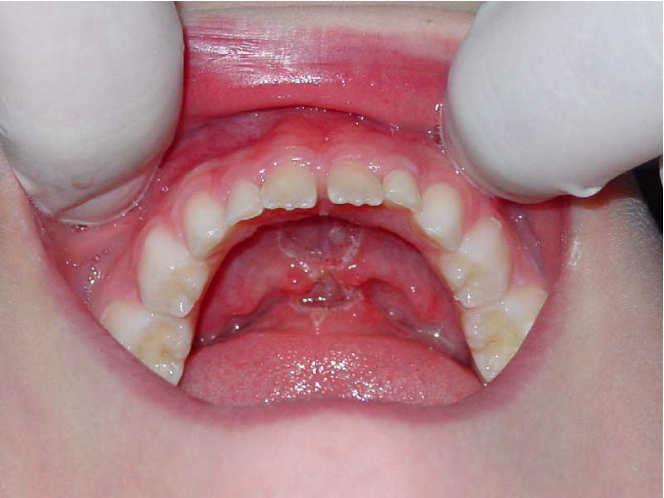

2

Dott. Stefania Cristalli